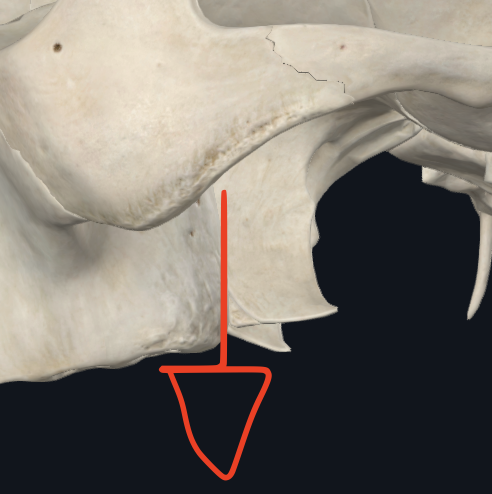

Apófisis condilar

Se puede semidislocar

Dividido en cabeza y cuello

Apófisis coronoides

Músculo temporal

Escotadura sigmoidea

Fosa retromolar

Ángulo maxilar

Une el borde inferior con el borde posterior

o Gonión